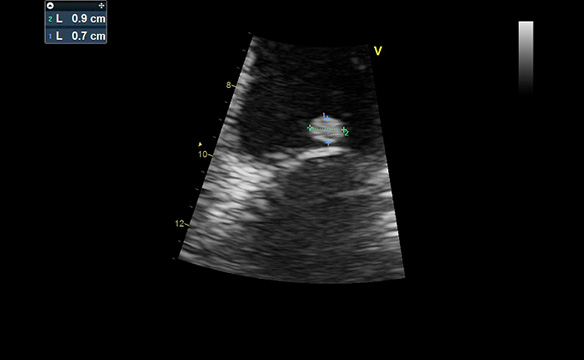

Paciente de 56 años de edad, sin antecedentes patológicos que consulta en nuestro centro a la Dra. Barr por episodio sincopal mientras se encontraba en baile.

TA : 120-80 mm hg. No soplos. Pulsos y pulmones normales. ECG normal. Afebril.

ECO DOPPLER y ETE, equipo Phillips 3D (Dra. Barr y Tec. En imágenes Lucia Vacas): imagen en Valva Mitral redondeada de 0.8 mm, muy móvil, sin compromiso de ecoestructura Mitral luego fue evaluado en consulta con Dr. Avegliano, confirmando la sospecha de que por las características de dicha masa puede corresponder a Fibroelastoma Papilifero. Dada la alta incidencia de embolia, se envía a Cirugía Cardiovascular.

Fecha: Nov. 2019

Aparato: Eco Doppler/ETE

Autor: Dra. Barr